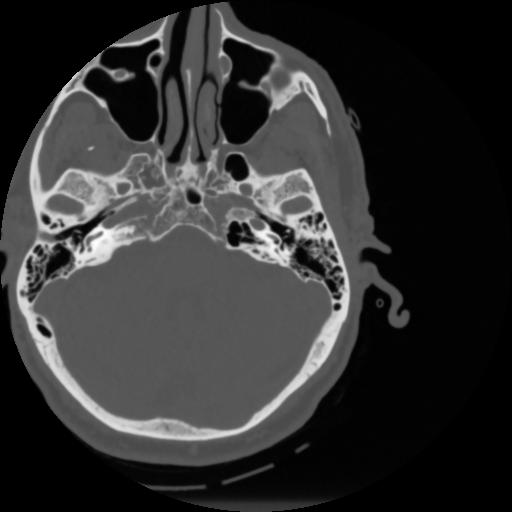

4 CEREBRO,,Vol,0.5,CEREBRO,,